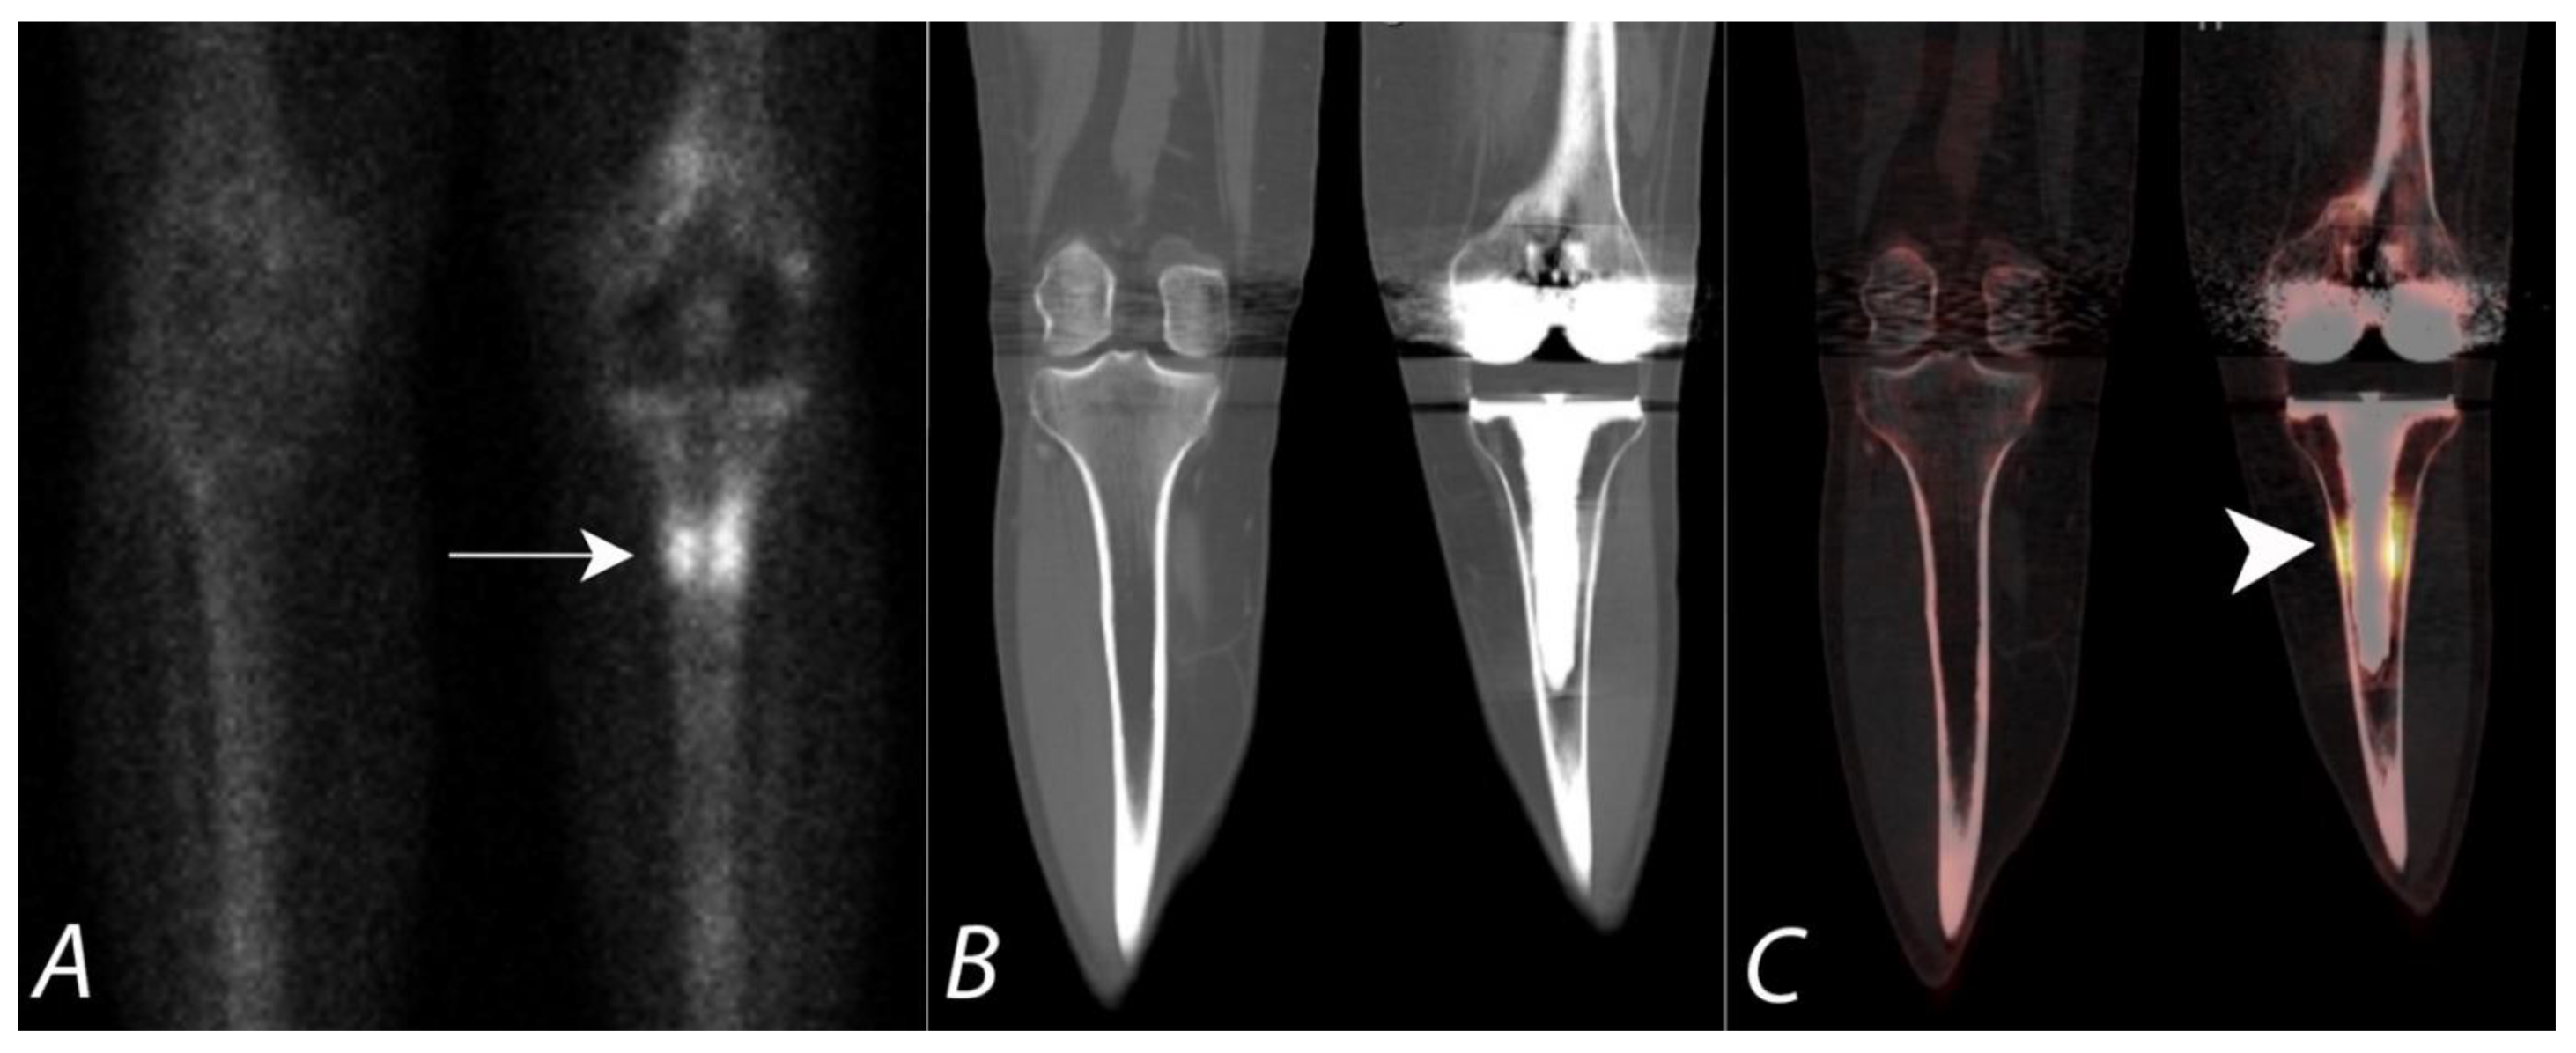

SPECT/CT has become a very useful technique in the evaluation of painful knee status post knee arthroplasty and has recently been proposed as the second line of imaging modality after MRI in these patients. Even in asymptomatic patients, radiotracer uptake on planar and SPECT bone scans, specifically around the tibial component of the arthroplasty, can be a normal finding, even many years after the procedure. The addition of the CT component to SPECT significantly increases the specificity and accuracy of diagnostic interpretation by improving accurate localization of the uptake to a specific anatomic location [92,93]. For example, identification of the granulomatous process on CT can be a cause for non-specific diffuse uptake on bone scans. Additionally, in the absence of any anatomic abnormalities on CT, localized radiotracer activity below the medial aspect of the tibial component can be interpreted as physiological with a greater degree of confidence. The addition of other follow-up evaluation procedures, specifically if infection is suspected, may be required for complete assessment of painful knee after arthroplasty. SPECT/CT has been shown to be a highly valuable modality in this subset of patients, with alteration of management approach in up to 85% patients [92,93] (Figure 9).

Figure 9.

Fifty-year-old female with a painful left knee prothesis. Anterior planar (A), coronal CT (B) and coronal SPECT/CT (C) images of a Tc-99m MDP bone scan of both knees demonstrate a prominent increased uptake in a band surrounding the midportion of the left tibial prosthetic stem. Plain AP radiographs demonstrate sclerosis without periprosthetic lucency. Findings are consistent with being related to altered biomechanical remodeling (similar to a stress fracture). There is no evidence for loosening or infection.